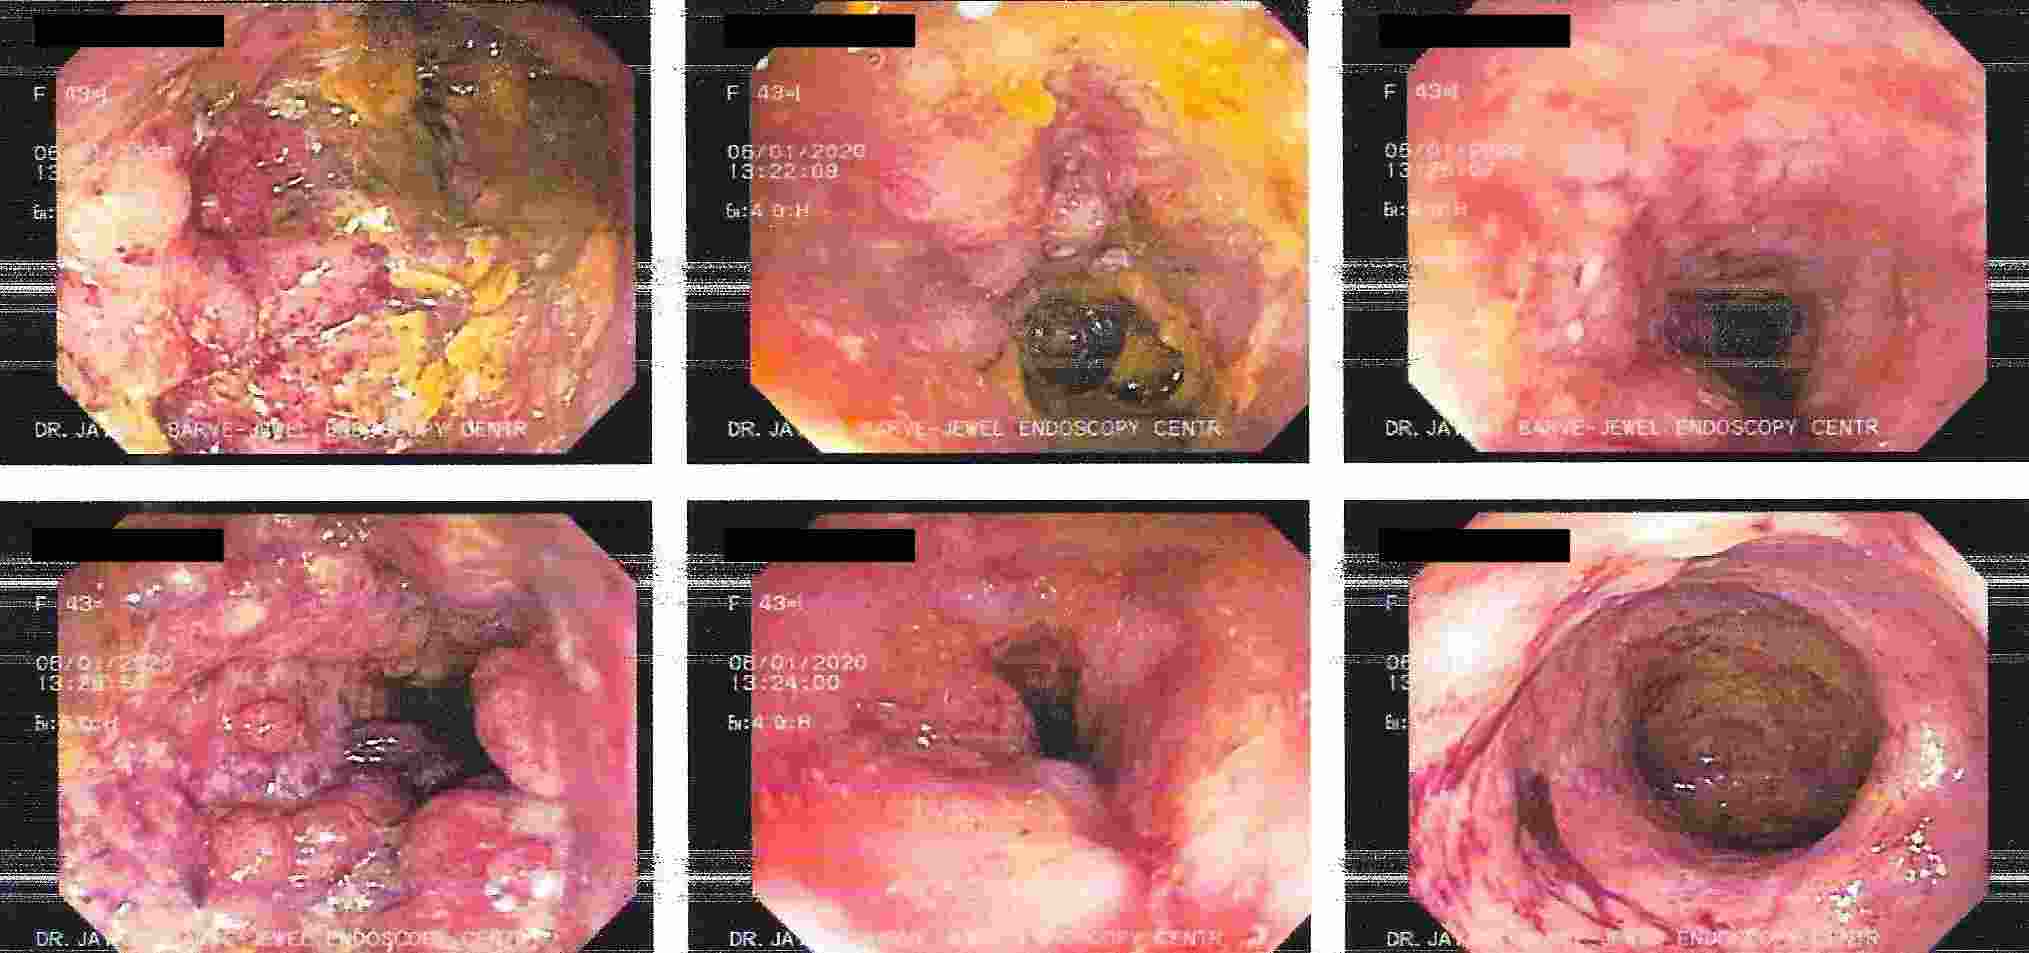

Altered bowel habits, watery or semisolid stools, gripping pain in abdomen, mucus and blood in the stool,

incomplete evacuation can all be due to a condition called as colitis. Colitis has got different causes

like ulcerative colitis, Crohn’s disease, infections, tuberculosis, amoebic colitis, bacillary dysentery and many more.

Corrcet diagnosis by Colonoscopy will allow patients to be treated properly.

IBD - Ulcerative Colitis

IBD - Crohn's Disease

Ulcerative Colitis

Ulcerative Colitis

Crohn's Disease